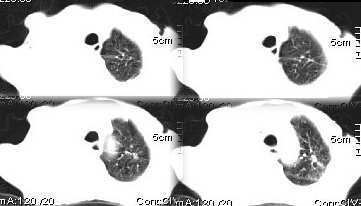

男,76岁,因心累,气紧加重,伴吐白色沫哝痰,偶尔有低烧,无盗汗。{门诊患者未见其它检查}

病灶在右上叶支气管的后段旁,成类圆形,约2.3厘米大小,其内见钙化密度区,病灶平扫为77,强化为87.左肺上叶尖后段沿血管支气管分布见小结节.我认为右上叶后段支气管开口有截断.我首先考虑是右中央型肺癌伴右恻大量胸腔积液,但左肺的病变我真的有的不好解释,希望各位战友继续讨论,不对之处望指出!!谢谢!!!

右肺毁损萎陷,其内可见钙化灶、残存空腔及支气管影。左上叶可见多发小结节影。纵隔左移,其内未见肿大淋巴结。右侧胸腔大量积液。考虑:肺结核并右肺毁损;右侧胸腔大量积液。

右侧大量胸腔积液伴右肺压迫性肺不张,上叶内是不是结核灶?

右上叶后段开口处可见约3cm·3cm大小的肿块,边缘较光滑,无明显分叶且有钙化,右上叶支气管后壁受侵不明显,加上左上叶病灶。我首先考虑肺结核,胸腔积液。右肺不张。还是建议支气管镜检查,或者胸水检查。